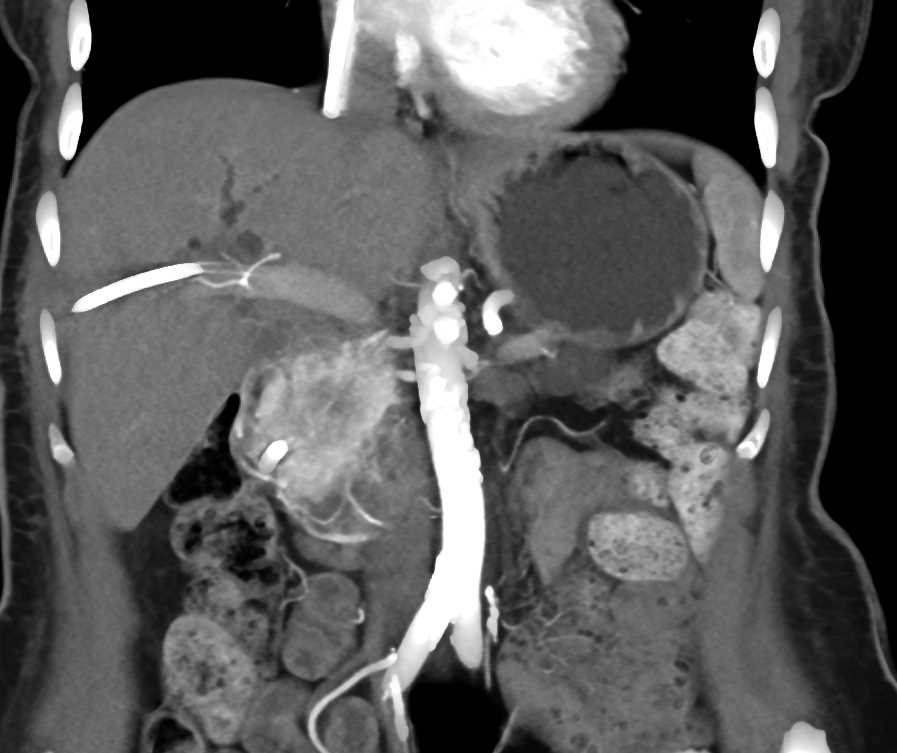

Pancreatic Adenocarcinoma with PV/SMV Occlusion Using Cinematic Rendering